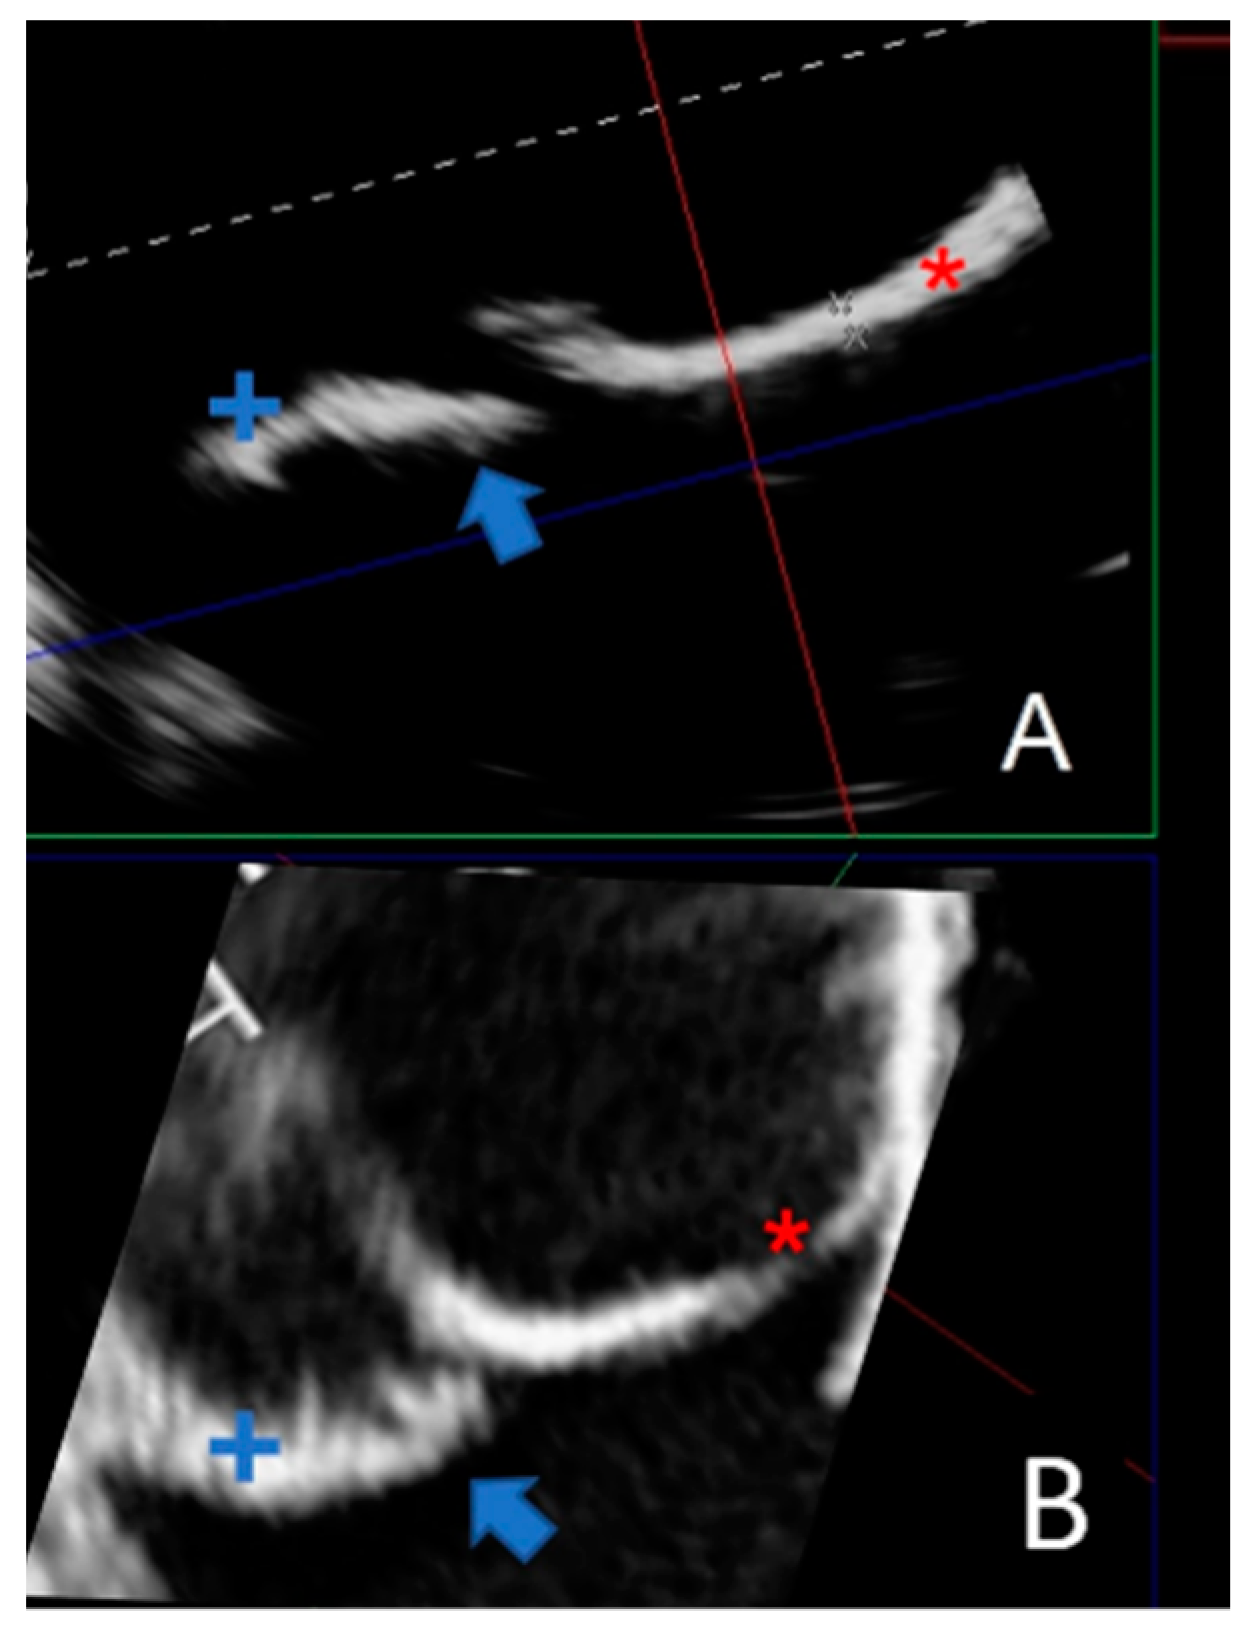

Due to their porous structure, the TPU and TPE models exhibit interesting echogenic properties. We compared the echogenic rendering with in situ images of the same valve (refer to Figure 9 and Figure 10). The valve structure was accurately depicted in both 3D and 2D views. Notably, the cusp in situ thickness measurements align with the model’s 0.3 mm thickness.

Figure 9.

The bicuspid aortic valve in a similar face-plan view. (A) View of the 3D printed model. (B) A 3D ultrasound view of the immersed model (with two thin aortic cusps marked with * and +). (C) A 3D ultrasound in situ view of the same valve in the patient, showing both cusps (+ and *).

Figure 10.

Comparing a 2D echographic view of the bicuspid aorta model to the in situ view. (A) A 2D ultrasonograph of an immersed bicuspid aorta model with two cusps (+ and *) and prolapse of one cusp (blue arrow). (B). A 2D in situ ultrasound in the same orientation as A, with two cusps (+ and *) and cusp prolapse (blue arrow).